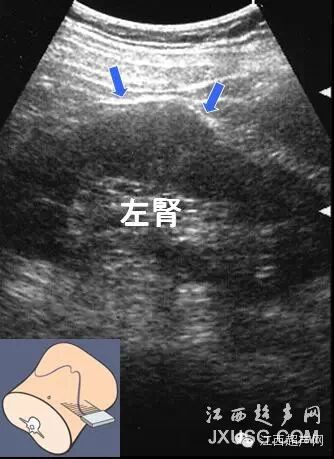

11.在看肾脏时,容易把正常肾的分叶看成肿块,有时是越看越象是肿块。

30.有的时候右侧卧位检查左肾时,打左肾中极会向外略向外突起,容易误诊为肾脏肿瘤。

彩超伪像是什么60个超声诊断中容易误诊的正常结构_https://www.jmylbn.com_新闻资讯_第9张